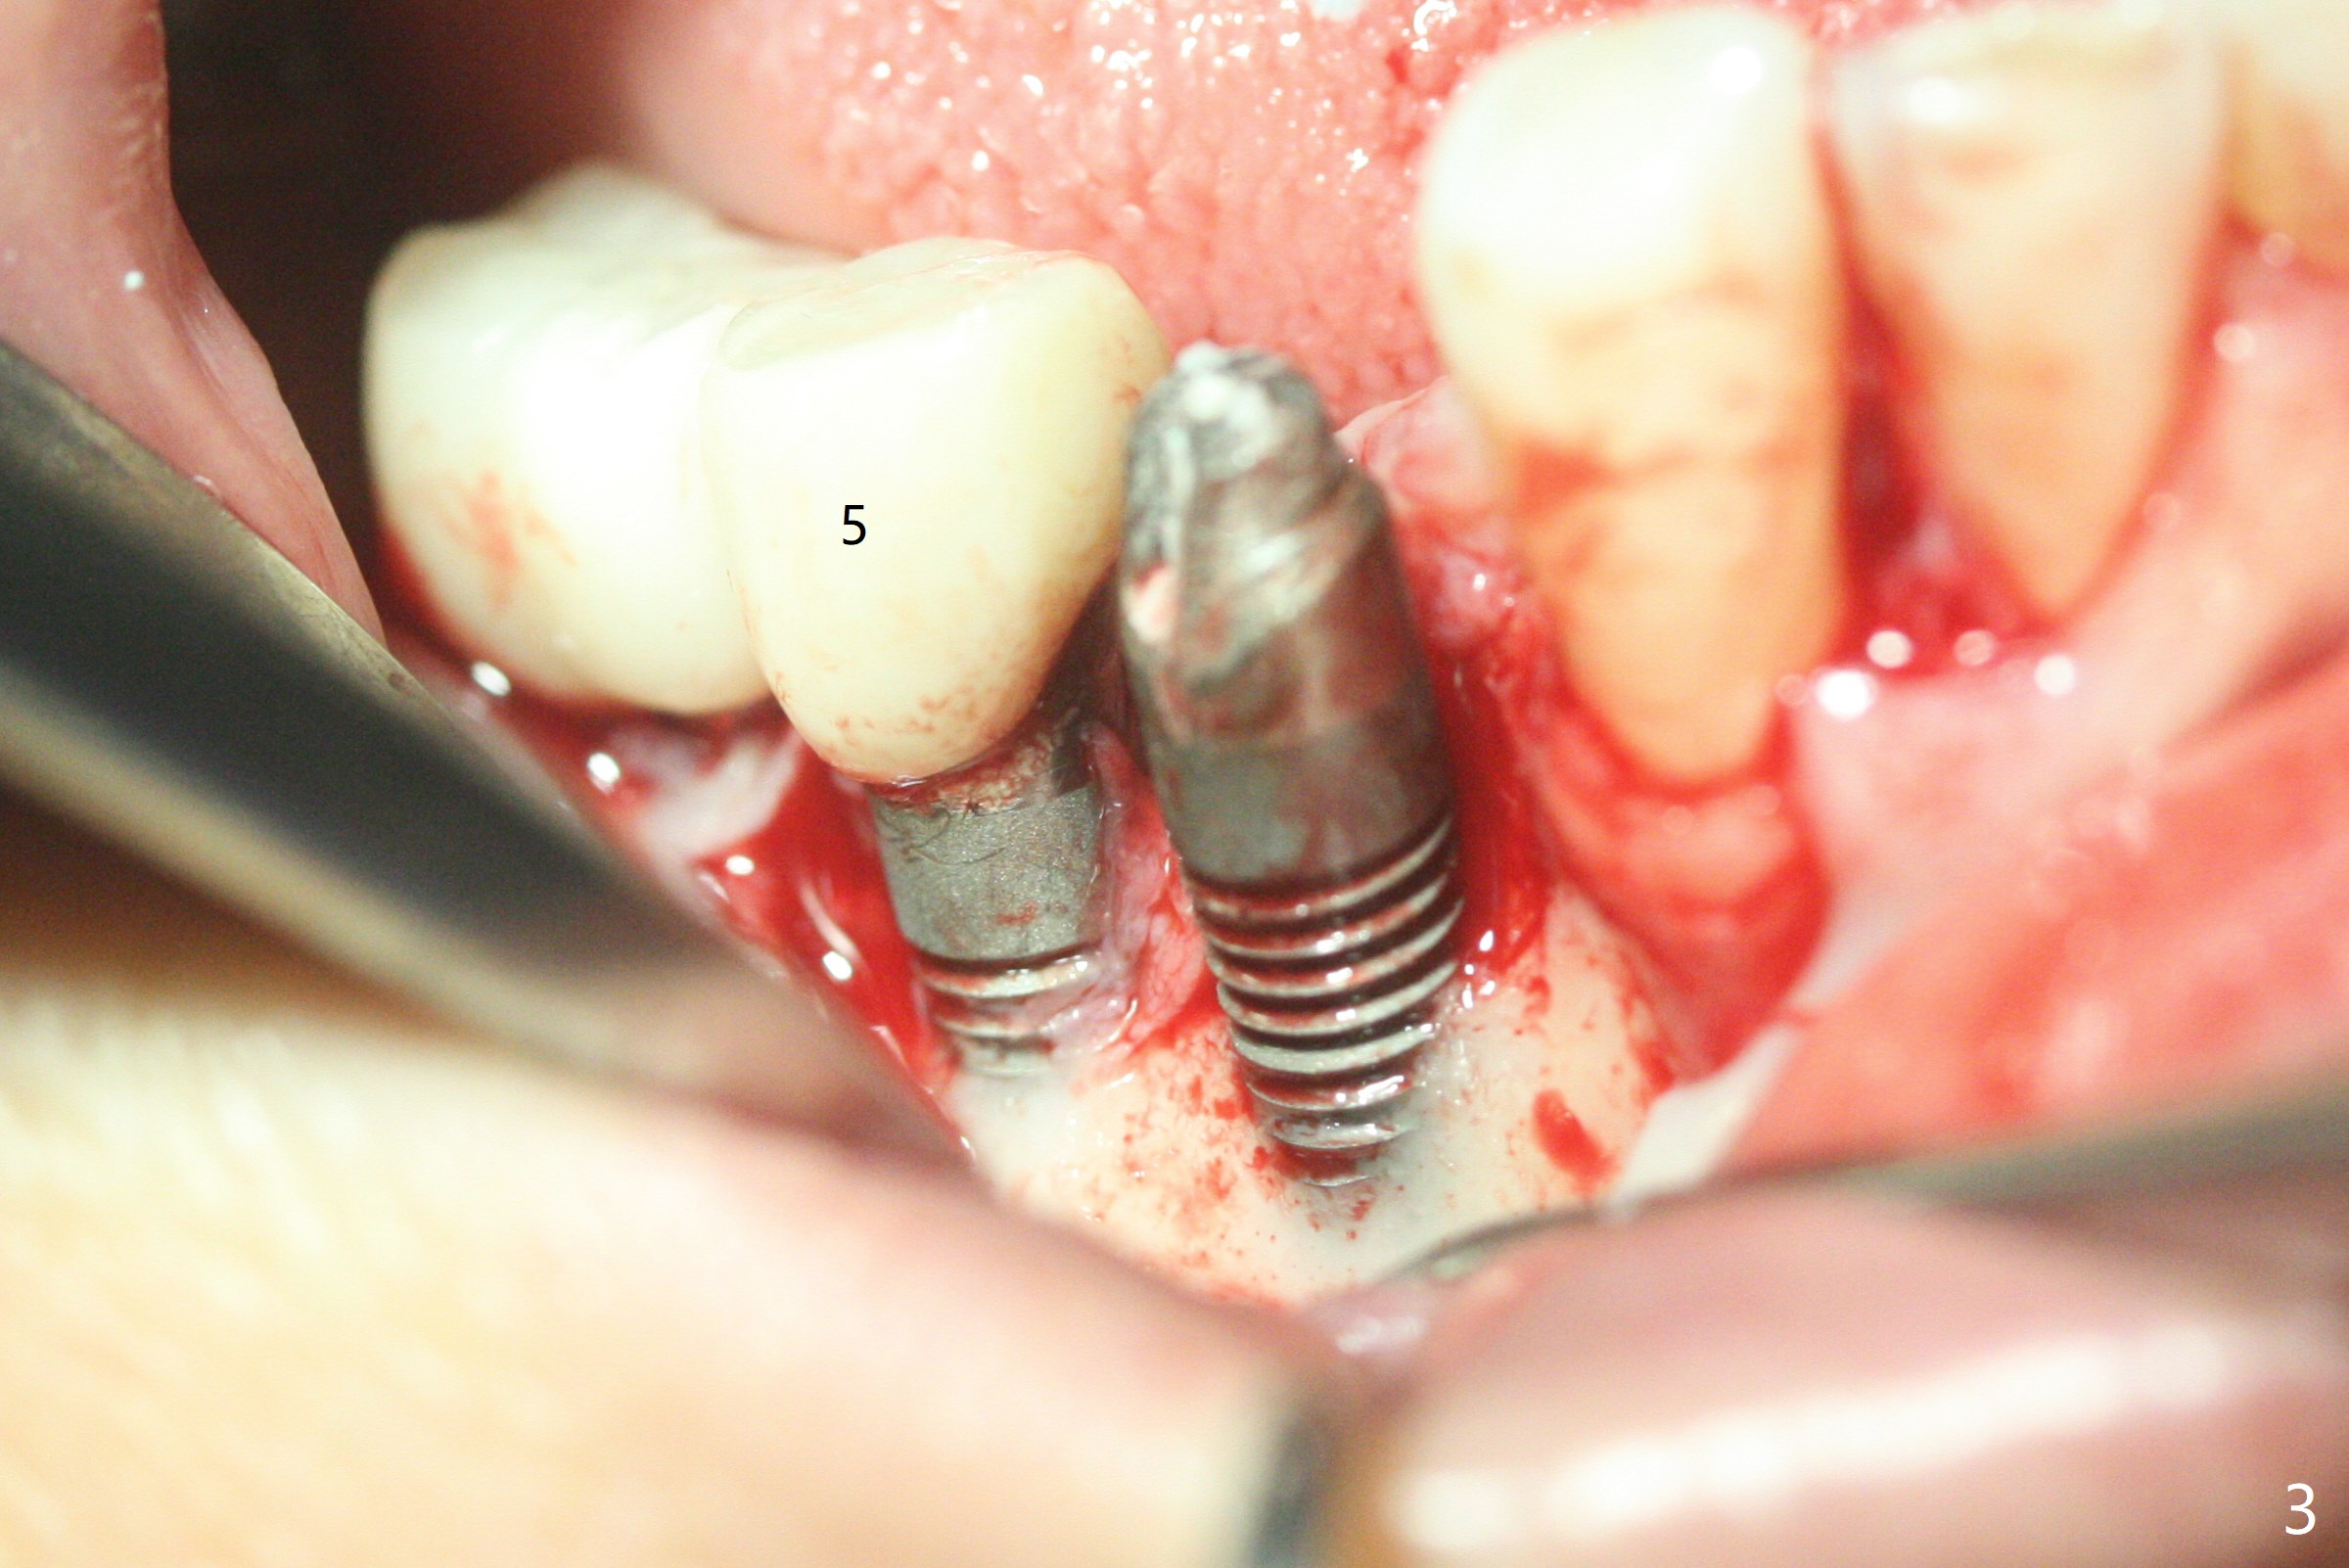

61岁女右下4(粘固后5.5年)植体周围炎(颊侧牙龈没有角化龈(图一:*)),因为颊侧种植(图二),翻瓣证实(图三),取出4.5毫米两段式植体,在舌侧骨质(图四:L)即刻植入2.5毫米一段式植体(图五),颊侧缺损植入大量粘性骨粉(图六:*),覆盖PRF膜后,缝合(图七),与图二对比,窄植体明显舌侧移位。术后一个月撤除牙周敷料(图八),并没有马上制作临时牙冠,让病人容易搞好局部卫生,促进伤口愈合(图九),术后三个月塞入龈线(图十:^),制备基台,植体在牙槽嵴中性位置(颊舌侧),但愿颊侧有足够再生骨质,覆盖植体螺纹。